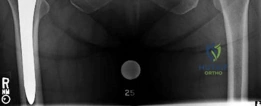

The intraoperative and immediate postoperative AP radiograph demonstrates excellent alignment of the components. The acetabular cup is appropriately inclined, and the AML stem is centered within the femoral canal, demonstrating a tight diaphyseal fit without evidence of cortical fracture.

The postoperative lateral radiograph confirms appropriate version of the acetabular component and central placement of the femoral stem within the medullary canal. The robust porous coating is visible engaging the diaphyseal cortices.